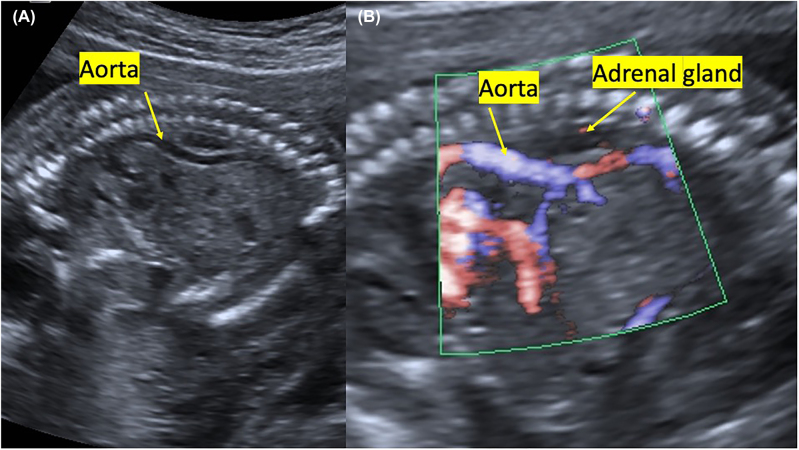

Case presentation: We report a case of bilateral renal agenesis diagnosed prenatally. We presented the ultrasound and pathology images of this fetus with a new sonographic sign, segmental anterior deviation in the abdominal aorta.

Conclusions: To our knowledge, this is the first reported case of a fetus with a segmental aortic anterior deviation.